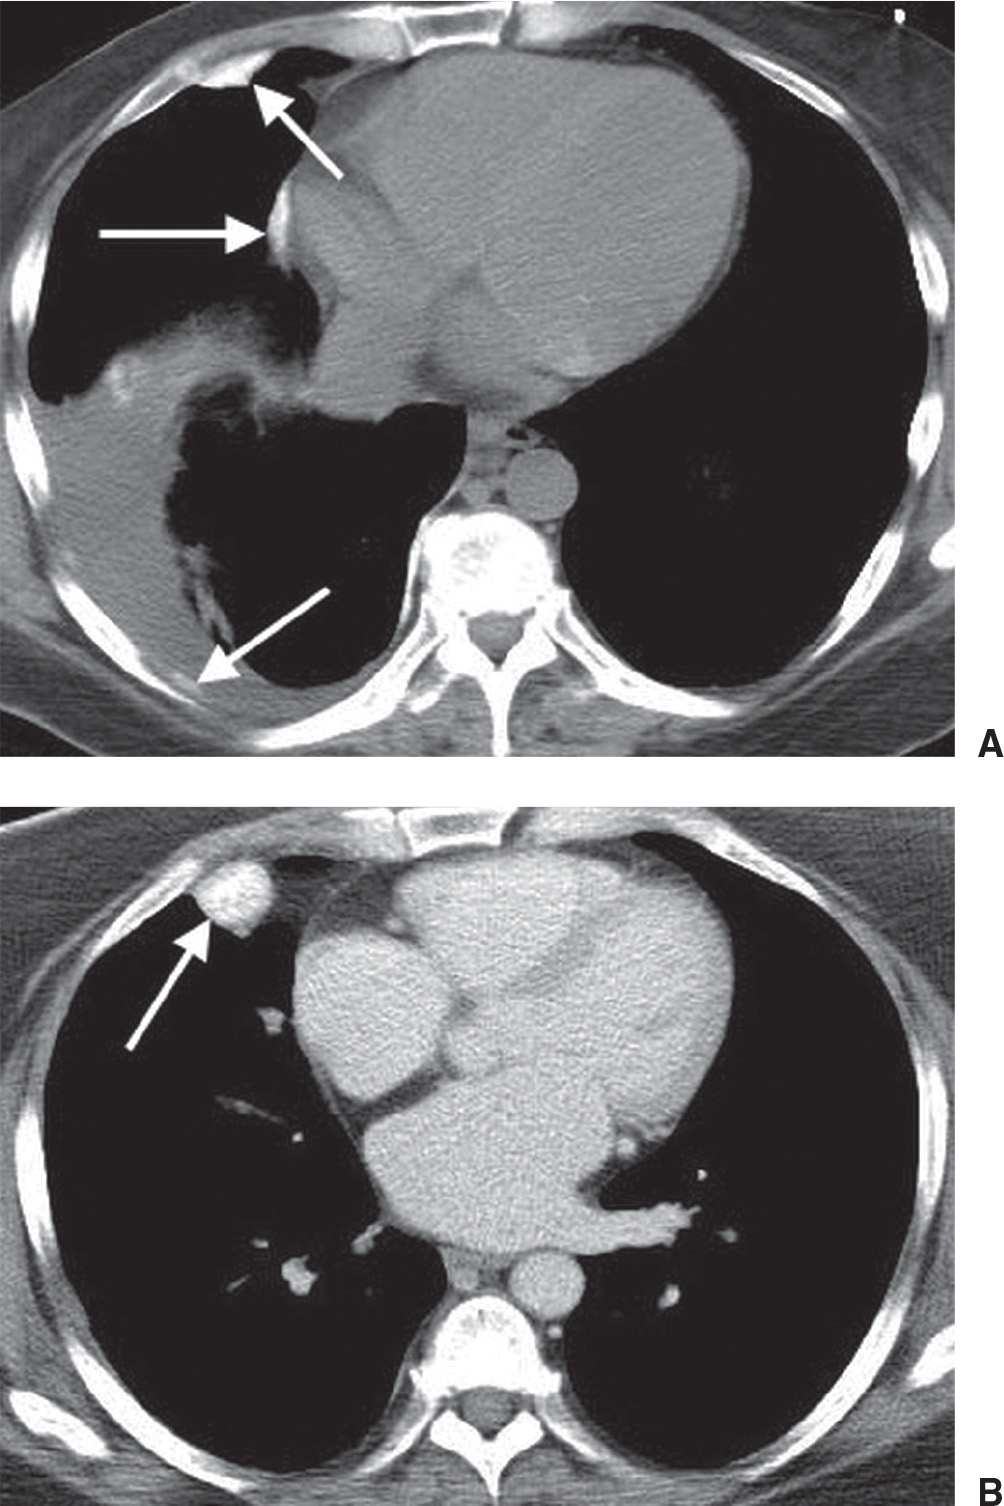

Split pleura sign on CT scan with thick pleural lining. Image courtesy Pleural Tag Sign Radiology By univariate analysis and multivariable adjustment, surgical history, tumour marker (tm), number of pleural tags, length of solid contact and obstructive inflammation were identified as independent risk predictors of pleural invasiveness (p= 0.014, 0.003, <0.001, <0.001, and 0.017, respectively). Pleural tags refer to slender bridges of soft tissue seen on ct scans that extend between masses in the lungs and. Pleural Tag Sign Radiology.

Split pleura sign. Enhanced CT of the chest shows a low attenuating Pleural Tag Sign Radiology Type 2 pleural tags on conventional ct images can increase the accuracy of early diagnosis of visceral pleural invasion by nsclc that does not abut the. Pleural tags refer to slender bridges of soft tissue seen on ct scans that extend between masses in the lungs and the pleura. By univariate analysis and multivariable adjustment, surgical history, tumour marker (tm),. Pleural Tag Sign Radiology.

Pleural empyema CT wikidoc Pleural Tag Sign Radiology Pleural tags refer to slender bridges of soft tissue seen on ct scans that extend between masses in the lungs and the pleura. Department of radiology, concord repatriation general hospital, concord, new south wales, australia. Juxtapleural lung nodules can be defined by their location within 15 mm of a pleural surface. Intrapulmonary lymph nodes are typically. By univariate analysis and. Pleural Tag Sign Radiology.